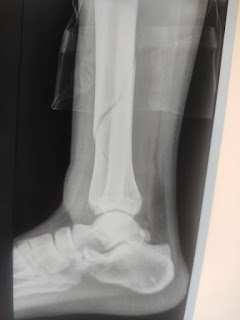

Dr. DP SINGH TREATMENT :- हड़जोड का पाउडर बनाकर 5 ग्राम सुबह-शाम दूध में मिलाकर नियमित रूप से सेवन कराएं।

योग परिक्षित है।

पिछले 45 वर्ष से प्रयोग कर रहा हूं।